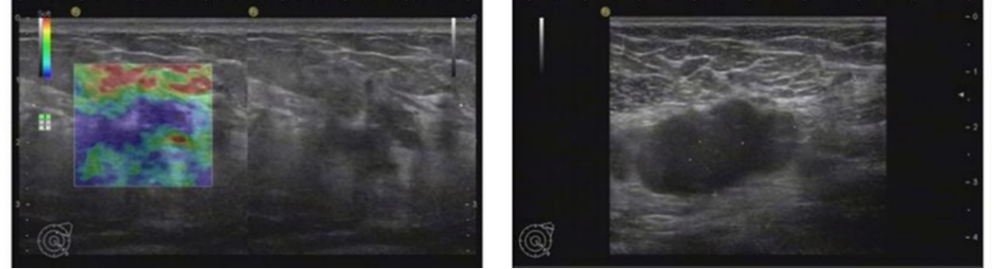

2019年10月乳腺彩超(术前):左乳实性占位(BI-RADS 4c级)。左腋下淋巴结肿大,考虑转移。

图1.乳腺彩超

本例患者术前评估左乳实性占位(BI-RADS 4c级)。左腋下淋巴结肿大,考虑转移。术后病理:ER(-),PR(-),HER2(3+),Ki67(30%)。由于患者的原因,未能做新辅助治疗,缺失了新辅助治疗后的再一次疗效评估,以及对辅助治疗的进一步决策。术后辅助治疗EC-THP(表柔比星+环磷酰胺,序贯多西他赛+赫赛汀+帕捷特),之后辅助曲妥珠单抗(赫赛汀)+帕妥珠单抗(帕捷特)靶向治疗完成1年治疗。在辅助靶向治疗后4月发现单发脑转移病灶。之后行左侧小脑半球肿瘤切除+颅底重建术。脑转移瘤瘤床区放疗。全身系统治疗:汉曲优+吡咯替尼+卡培他滨作为二线治疗,随访中已有15月的PFS,目前仍是CR状态。